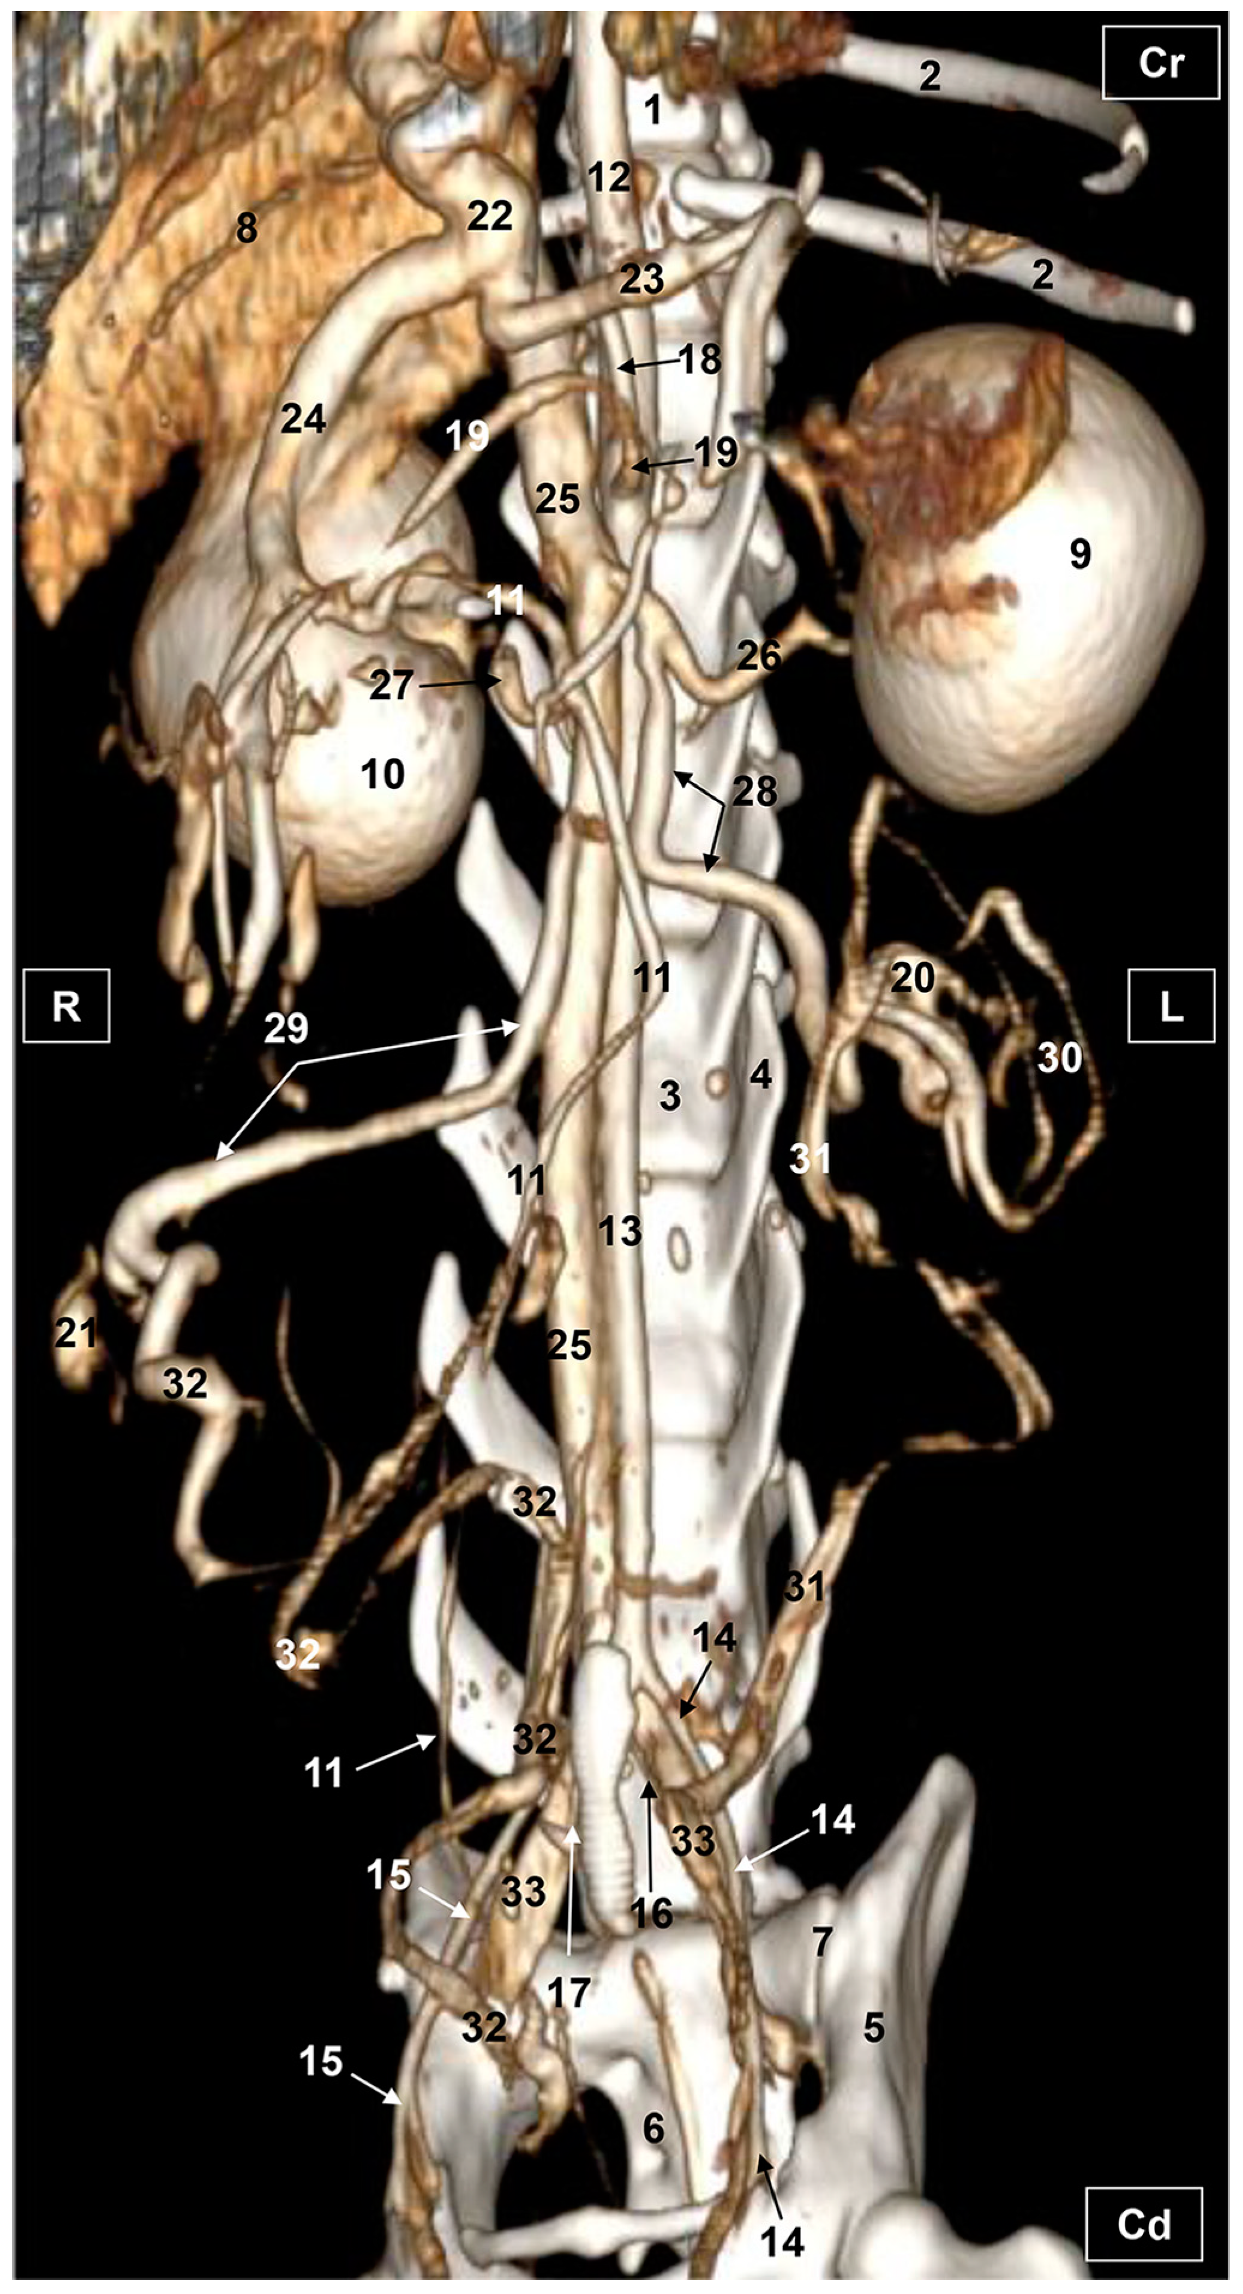

3.1. Gross Dissections

3.1.1. Arterial System

3.1.2. Venous System

3.2. Computed Tomography Angiography and 3D Printing

3.2.1. Arterial System

3.2.2. Venous System